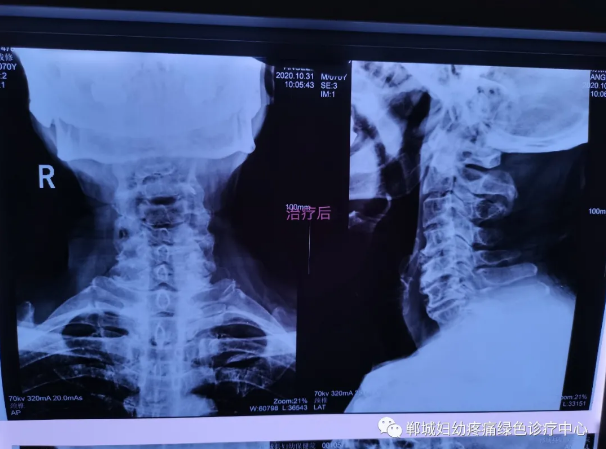

治療前李老師頸椎X線檢查影像

1個(gè)療程治療后頸椎X線檢查對比